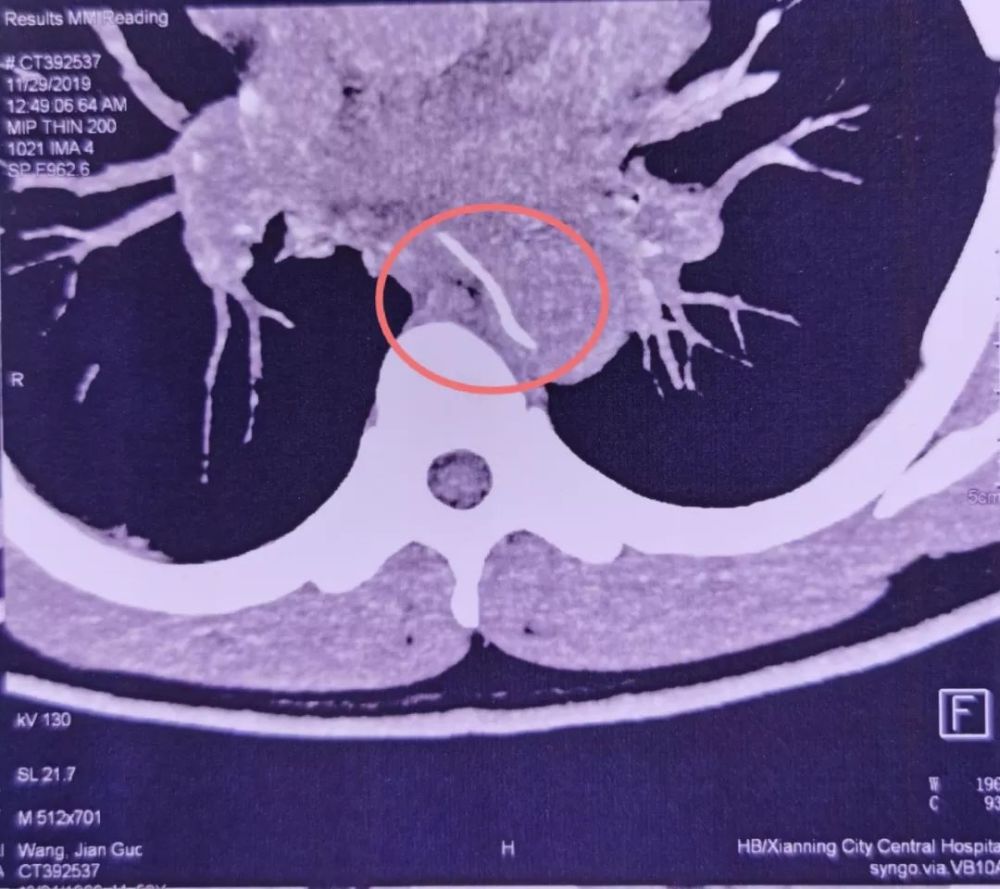

没想到过了两天 , 他突然感到剧烈胸痛 。 CTA检查发现 , 一根鱼刺样的异物卡在了食管内 , 且已刺穿食管壁 , 一头扎进了胸主动脉 。

文章插图

图源:武汉大学人民医院

11月29日 , 林先生来到了武汉大学人民医院急诊科就诊 。 魏捷教授检查发现 , 鱼刺像一把圆月弯刀 , 横插在食管和胸主动脉附近 。 如果盲目拔出 , 必定会形成主动脉破口 , 发生大出血 。